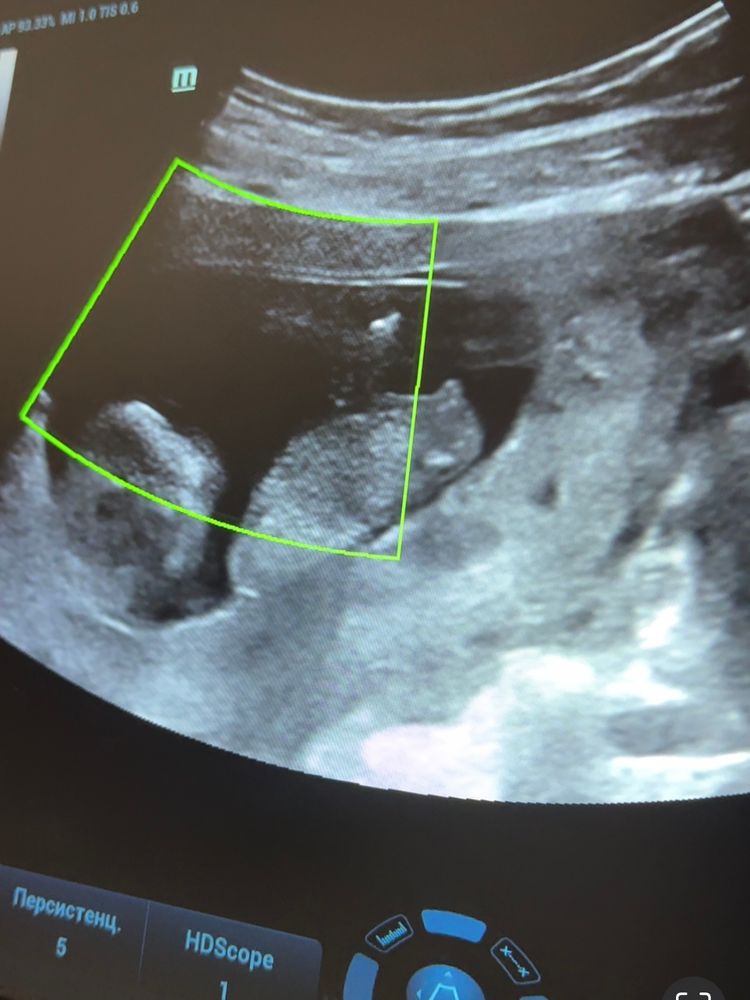

Айка в Благополучная беременность 2 года Мальчик или девочка? УЗИ, КТГ, доплер Кто нибудь разбирается в углах наклона? Как думаете, кто у нас тут?🤔 Посмотрите еще 20 записей на эту тему Отменить Ответить ♥ Ангелочек ♥ Девочка 27.11.2023 Ответить Юля Девочка. 26.11.2023 Ответить Не обязательно На первом фото мальчик, на втором девочка 🤭😅 26.11.2023 Ответить Мария А как вы это понимает? 26.11.2023 Ответить elena Девочка 26.11.2023 Ответить Виктория Девочка 26.11.2023 Ответить Svetlana Девочка похожа 26.11.2023 Ответить Док Валерия Мой хрустальный шар говорит что это девочка 26.11.2023 Ответить 31 ДПП 🤍 УЗИ Два желтых тела и одно плодное яйцо Чаты Беременных Выберите чат: Январята-2026 Февралята-2026 Мартята-2026 Апрелята-2026 Майчата-2026 Июнята-2026 Июлята-2026 Августята-2026